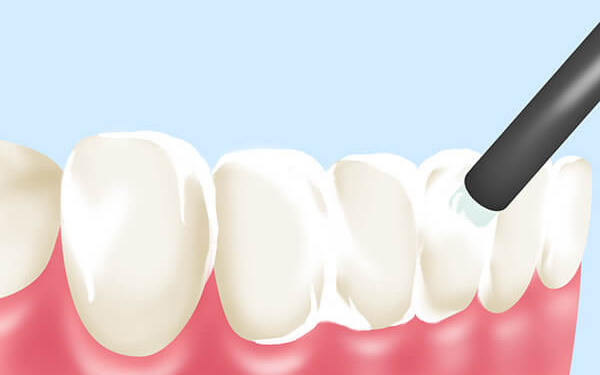

虫歯感染部位がピンポイントでわかる「う蝕検知液」

歯周ポケットの測定は、歯周病の進行度を確認するために欠かせない検査です。歯科医院で「少しチクッとしますね」と言われながら歯茎を器具で軽く刺激された経験がある方もいるかもしれません。これは「プロービング」と呼ばれる検査で、歯と歯茎の間にある隙間(歯周ポケット)の深さを測定し、歯周病の状態をチェックするものです。

歯周病治療を効果的に進めるためには、歯周ポケットの測定を定期的に実施し、歯周病の状態を正確に把握する必要があります。